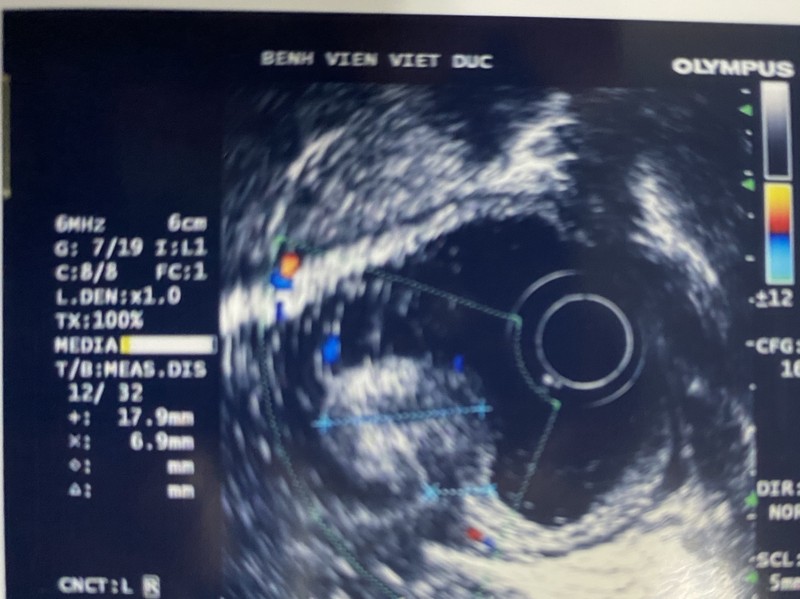

Ngay sau đó, các bác sĩ đã tiến hành siêu âm nội soi để xác định khối u đã phát triển đến lớp nào trong thành ống tiêu hóa để đưa ra phương pháp điều trị phù hợp. Sau khi hội chẩn với các bác sĩ nội soi, ê kíp phẫu thuật đã quyết định thực hiện phương pháp can thiệp nội soi hiện đại “cắt tách niêm mạc” – ESD (Endoscopic Submucosal Dissection) để loại trừ tổn thương, bảo tồn dạ dày cho người bệnh. Nếu thủ thuật nội soi thất bại thì sẽ phẫu thuật cắt dạ dày sau.

Hình ảnh siêu âm của bệnh nhân (Ảnh: Bệnh viện Hữu nghị Việt Đức)

BS. Chu Nhật Minh - Trưởng khoa Nội soi Tiêu hóa, Bệnh viện Hữu nghị Việt Đức - cho biết: Bệnh nhân T. vào viện trong tình trạng bị tổn thương dạng u lan tỏa - LST (laterally spreading tumor) theo phân loại Paris 2008 về các tổn thương tiền ung thư với cấu trúc bề mặt gồm các biểu hiện như: phì đại, quăn queo, nhìn thấy mạch máu nhỏ, phân bố không đều, chảy máu rỉ ở vài điểm, ranh giới rõ,… Các bác sĩ tiến hành nội soi cắt tách niêm mạc cho bệnh nhân.